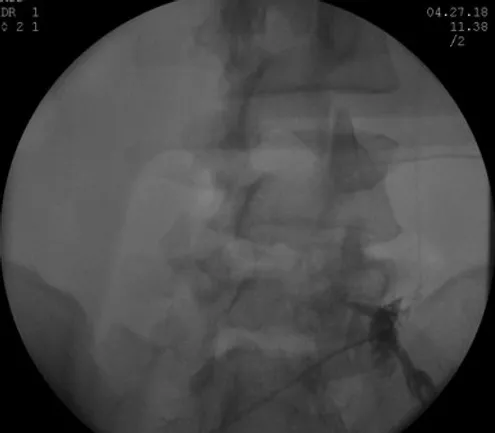

Decided to proceed with Right sided L5 and S1 Transforaminal Epidural Steroid Injections

- 1st on 09/15/2017 > 70% relief of symptom

- 2nd on 10/20/2017 > 80% relief of symptom

- 3rd on 11/21/2017 > 90% relief of symptom

First Lumbar Bilateral L5-S1 Transforaminal Epidural Steroid Injection 11/01/2016 > 30% Relief

Second Lumbar Bilateral L5-S1 Transforaminal Epidural Steroid Injection 11/29/2016 > 50% Relief

Third Lumbar Bilateral L5-S1 Transforaminal Epidural Steroid Injection 12/27/2016 > 70% Relie